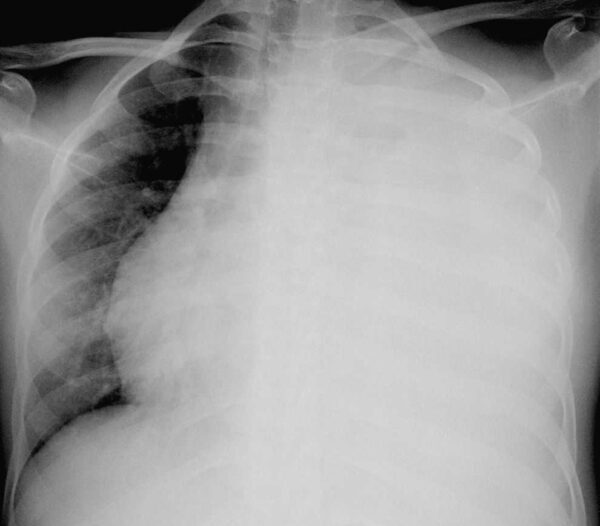

Debe haber cerca de 75 a 100 ml de líquido pleural en el surco costofrénico posterior para ser visibles en la imagen lateral y 175 a 200 ml en el surco costofrénico lateral para delinearse en la imagen frontal de una radiografía de tórax en posición supina. El líquido pleural puede quedar atrapado (tabicado) por adherencias pleurales y formar en consecuencia acumulaciones poco comunes a lo largo de la pared lateral del tórax o dentro de cisuras pulmonares.

El derrame pleural masivo que causa opacificación de la totalidad de un hemitórax se debe con mayor frecuencia a cáncer, pero puede observarse en la tuberculosis y otras enfermedades.